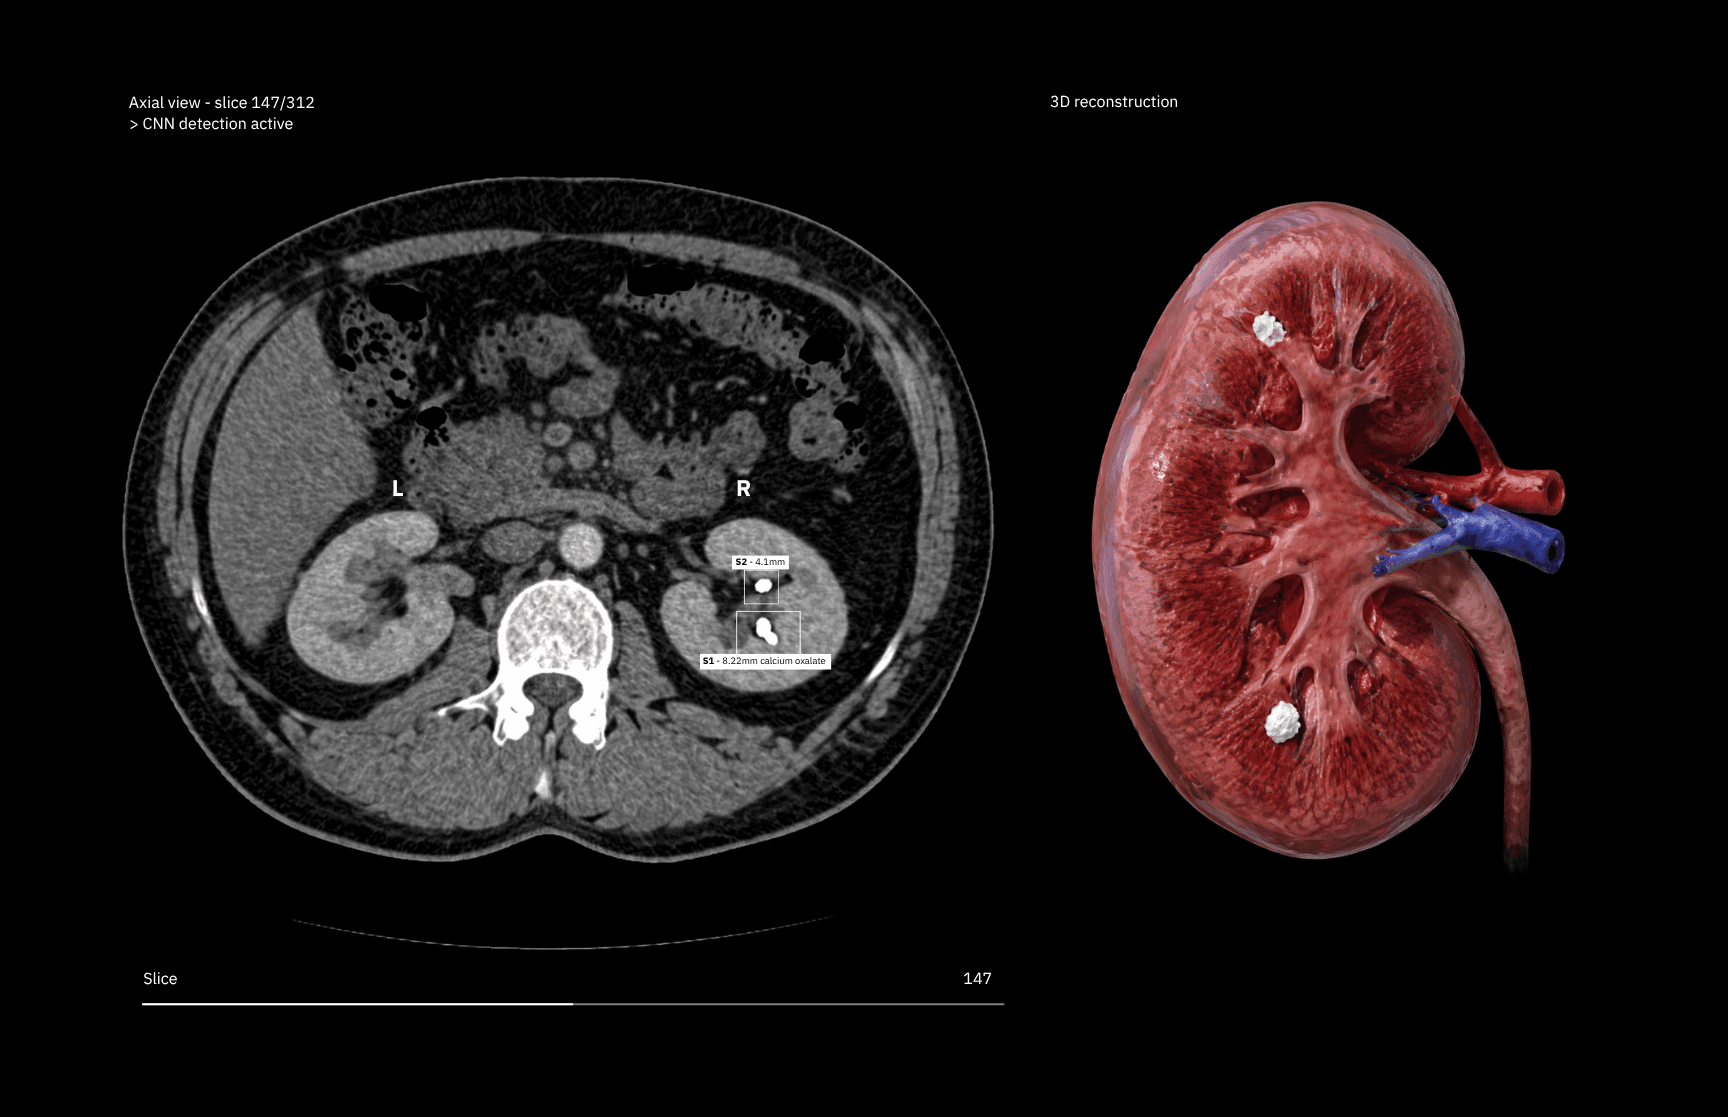

We partnered with Lithuania's leading hospital to build an AI system that reads FTIR spectroscopy results in minutes, replacing the hours-long manual process that left nephrologists working from error-prone stone composition analyses.

We built an AI system that automates the interpretation of FTIR spectral data. The core mechanism compares a patient's kidney stone spectrum (the unique infrared absorption pattern of their sample) against a comprehensive reference library of known stone compositions. This identifies the best matches and scores their likelihood.

The ML models were trained on hundreds of existing FTIR spectra to learn the spectral signatures of different stone types: calcium oxalate dihydrate, uric acid, struvite, and mixed-composition stones among them. Rather than outputting a single binary classification, the system assigns probability scores across candidate compositions to give clinicians a confidence-weighted result they can act on immediately.